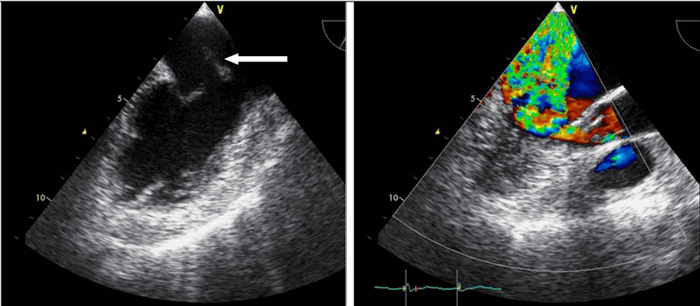

Для облегчения выявления турбулентного движения (завихрений) существует порог скорости, выше которого происходит изменение цвета (во многих аппаратах это зелены). «Мозаичный» узор на участке турбулентного потока позволяет легко установить регургитацию (смену направления движения), что помогает определить степень недостаточности клапанов.

5. Недостаточность аортального клапана диагностируют по появлению диастолического регургитантного потока в выходном тракте левого желудочка.

Градации величины регургитации:

1 степень (+) - регургитантный поток непосредственно под створками аортального клапана;

2 степень (++) - регургитантный поток распространяется до уровня передней створки митрального клапана;

3 степень (+++) - регургитантный поток распространяется до уровня папиллярных мышц;

4 степень (++++) - регургитантный поток регистрируется в полости левого желудочка.